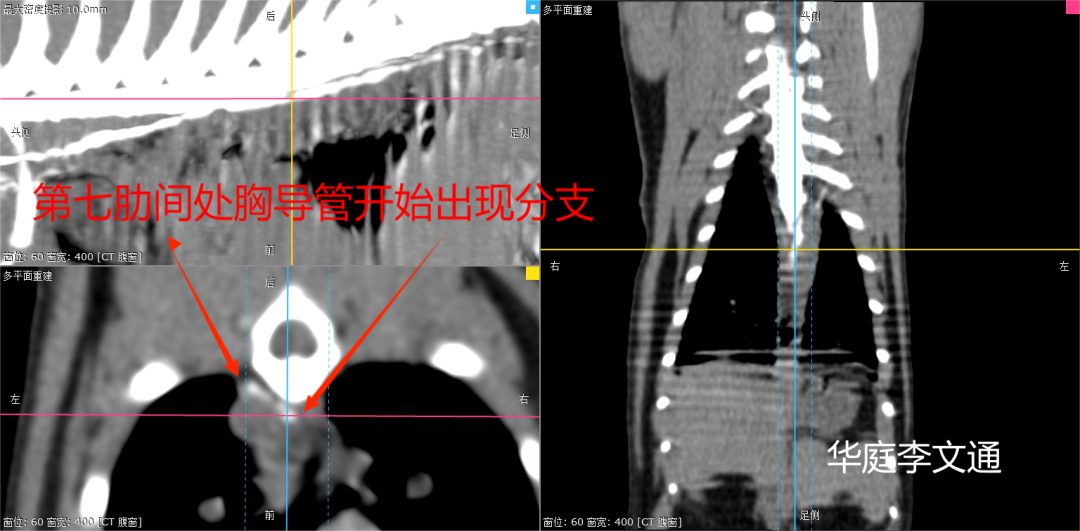

宠壹堂外科高阶第46期学员 李文通 ◆师从李永岐 ◆天津华庭动物医院医生 ◆宠壹堂医疗班讲师 ◆擅长兽医高阶影像诊断、软组织外科、复杂骨科、膝关节手术 01 病例信息 品种:狸花猫 性别:雄性 体重:4.5kg 年龄:2岁 主诉:7月初在外院确诊乳糜胸,体重逐渐减轻;外院2周内胸腔穿刺抽吸乳糜液2次,第1次为乳白色300ml,第2次为“草莓奶昔色”250ml,抽吸乳糜液前张口呼吸、频率浅快、舌色发绀,抽吸后有所改善但仍腹式呼吸急促,抽吸后乳糜液依旧分泌。自发现后主人一直喂食芦丁片。首诊医生转诊至我院。 体格检查:腹式呼吸、呼吸浅快,体态评分3(9分制),右侧胸廓听诊无呼吸音,叩诊呈水平浊音,左侧胸廓听诊呼吸音减弱。 02 术前化验室检查 血常规五分类: 血液生化检查: 影像学检查心超: 心包膜增厚且回声增强 03 术前ct CT平扫可见右侧胸腔被软组织衰减影填充,左侧重力侧可见软组织密度影;胸膜增厚。 04 诊断与治疗 诊断: 本例病例的诊断比较简单,首先需要考虑的就是胸腔积液的鉴别诊断。可以经胸腔穿刺采样后对液体进行检查,乳糜胸胸腔积液其性状为:浑浊、不透明、乳状(当混有血液时会变成草莓色);比重一般>1.025,蛋白质>20g/L,细胞数在1000-17000/ul(以小淋巴细胞为主);积液甘油三酯>血浆甘油三酯,积液胆固醇<血浆胆固醇。 治疗方案: 由于动物长期保守治疗无效且已出现心包炎与胸膜纤维化,最需要考虑的是手术方案。目前临床常用的手术方案有: 一、胸导管结扎 二、部分心包切除 三、乳糜池破坏 四、乳糜池和胸导管栓塞 五、经皮分流阀引流 六、胸腹腔引流 七、大网膜引流 本案例选择手术方案为胸导管结扎+部分心包切除。 手术准备 第十肋间开胸、肋间阻滞 切开胸膜后大量乳糜涌出 分离主动脉与交感神经干间组织,钛夹集束结扎 第五肋间开胸(心包炎、胸膜纤维化) 心包炎 心脏受限 部份心包切除后,心脏恢复正常搏动 部分心包切除后 心脏恢复正常跳动 胸腔引流管放置 术后即刻X光 术后第五天X光 术后第7天X光 术后第三周X光 术后用药:抗生素1天2次,奥曲肽8小时1次。 胸腔引流管术后抽吸:前3天乳糜液逐步减少;术后4-5天无乳糜产生,抽出清亮液体;术后第6天抽出5ml清亮液体,小于2ml/kg/d;术后第七天撤掉胸腔引流管;术后第八天拆线出院。 术后第八天呼吸状态非常平稳 05 病例讨论 乳糜胸是由于各种原因流经胸导管回流的淋巴乳糜液外漏并积存于胸膜腔内。 血浆中的脂类不溶于水,不能以游离的方式运输,只能与蛋白质结合在血浆中转运,中短链的脂肪酸经乳化后经门静脉入血,而长链脂肪酸只能与载脂蛋白、胆固醇等结合成乳糜微粒,经淋巴管入血。 淋巴管是收集淋巴回流的管道,是血液循环的辅助结构,最终汇入左颈静脉或锁骨下静脉。胸导管是全身最大的淋巴管,所以说任何引起静脉高压的的原因都会造成淋巴液回流受阻,导致泄露到胸腔。 胸导管从横膈膜膈脚起始,猫胸导管在主动脉与奇静脉之间的左侧,犬胸导管在右侧,至第五胸椎后在左侧交叉,所以猫胸导管结扎开口在左侧,犬胸导管结扎在右侧开口。 下图是笔者做的猫(不是同一只猫)经趾枕胸导管造影CT扫描的图像,可以清晰的看到胸导管的走向、泄漏点。 通过胸导管造影可以看到,胸导管分支在第七肋间开始汇合,汇合前一根分支在主动脉左侧,另一根在主动脉右侧。 胸导管到达我们肋间开胸处(第十肋间)时可以发现主动脉右侧的胸导管要粗于主动脉左侧,所以说我们在进行胸导管集束结扎时,一定要从主动脉正中开始分离,确保将两根胸导管同时扎住,避免遗漏。 另一点需要注意的是进行心包切除时,要避免仅心包切开而不切除,切开后的心包后续可能会勒住心脏,造成心脏扩张受阻。 术后的疼痛管理同样重要,疼痛会进一步使动物通气受阻,肋间阻滞和胸模内镇痛会减缓动物的疼痛。